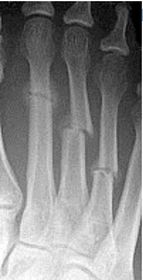

Describe the alignment of metatarsal 2 | There is no angulation nor displacement of the distal segment relative to the proximal segment. |

Describe the alignment of metatarsal 3 | The distal segment is displaced laterally (50% apposition) and angulated medially. |

Describe the alignment of metatarsal 4 | The distal segment is displaced laterally (75% apposition) but there is no apparent angulation. |

Describe the tubulation of the metatarsals | Metatarsals are overtubulated - decreased girth. |